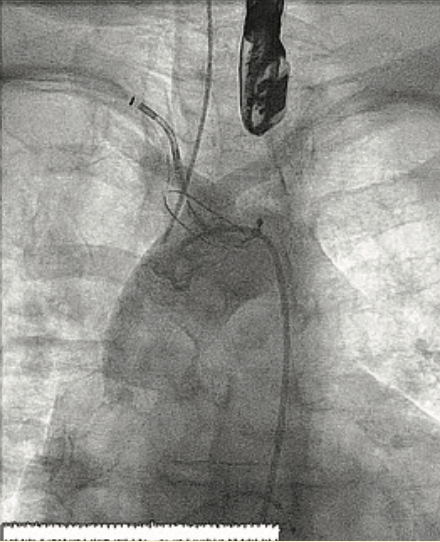

We planned to use cerebral protection during the case upfront, but the patient was known to have anomalous origin of her bilateral carotid arteries off of a single branch from the aortic arch, separate from the right brachiocephalic, and an anomalous insertion of the brachicephalic to the distal arch (Figure 2). We performed an aortic arch angiogram using a 15 cc contrast injection through a 5 French (Fr) pigtail with the ACIST CVi system (ACIST Medical) (Figure 3, Video 1) to guide the cerebral protection device from the anomalous brachiocephalic to protect the carotids. We proceeded with laceration of the left coronary cusp aortic valve leaflet. Aortic root angiography was performed using the same 5 Fr pigtail and a 10 cc contrast injection (Figure 4), then coronary angiography to identify the left coronary cusp (Figure 5). The optimal alignment of the left coronary cusp was determined by using a 6 Fr Amplatz left (AL) 1 guide catheter and a 6 cc injection with a lower pressure injection (Figure 6, Video 2). Finally, after the laceration was completed and the valve deployed (using small test injections from the ACIST contrast injector) (Figure 7, Video 3), we performed peripheral angiography with the 5 Fr pigtail advanced from the contralateral iliac artery to ensure adequate hemostasis of the large 14 Fr sheath access site (Figure 8, Video 4).